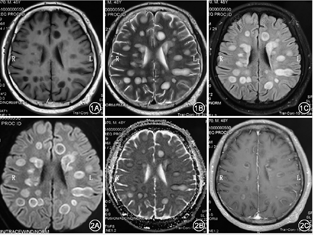

血常规:中性粒细胞0.777,淋巴细胞0.186,嗜酸粒细胞0.001,血红蛋白111 g/L,血小板计数110×109/L;尿常规:葡萄糖++,尿蛋白+;大便培养:菌群失调,有酵母样真菌生长;红细胞沉降率22 mm/h;补体:C3 0.72 g/L(0.8~1.6 g/L),血清免疫球蛋白G 5.92 g/L (7~16 g/L),CD20细胞105个/μl。血生化、凝血常规、便常规、甲状腺功能4项、术前4项、自身抗体、风湿4项、抗角质蛋白抗体、男性肿瘤全项、真菌D-葡聚糖、病毒系列均为阴性。脑脊液IgG合成率12.3 mg/d(-9.9~3.3 mg/d),血清及脑脊液寡克隆区带:阴性,抗MOG抗体IgG阴性,脑脊液蛋白1.1 g/L,脑脊液细胞学示:脑脊液可见12个淋巴细胞,13个单核细胞,3个嗜中性粒细胞。脑脊液二代测序阴性。肺CT(6月3日):①两肺下叶灌注不足;②心包少量积液;③两侧胸腔少量积液; ④主动脉硬化。颅脑CT:幕上脑白质多发低密度病变。入院MRI:双侧大脑半球多发异常信号,弥散受限符合脱髓鞘病变,感染继发?不除外脱髓鞘病变,请结合临床(图1,图2)。认知筛查:认知异常(欠合作),简易智力状态检查量表(mini-mental state examination,MMSE)8分,蒙特利尔认知评估量表(Montreal cognitive assessment,MoCA)2分,画钟检测0分。脑电图:中度异常,基本节律9 Hz,各导联混有大量中高幅3~7 Hz慢波及较多低幅18~ 28 Hz快波,尤以前头部导联为著。

根据McDonald标准2017版,本例患者1次发作,通过MRI证实了DIS(图1,图2),通过MRI增强扫描同时出现增强病灶与非增强病灶证实DIT(图2C),脑组织病理回报脱髓鞘病变,诊断:中枢神经系统脱髓鞘,多发性硬化。

影像学是MS诊断的关键之一,近年来诊断标准的修订愈显MRI的重要性。本例患者单个MRI切面上独立病灶最多达23个,实为罕见,大多分布于侧脑室旁,少数位于额颞顶枕叶,类圆形环状或结节状T1低信号T2高信号FLAIR高信号影,边缘清晰,大者约2.6 cm×1.6 cm,增强扫描初期部分强化,闭合环形强化或者开环样("C"形)强化,而后者多见于亚急性期;急性期以细胞水肿为主,DWI中心呈低信号,病灶周边呈环形高信号,其ADC值相对减低,称"晕环征",考虑为急性期MS病灶边缘聚集大量巨噬细胞,细胞外间隙缩小,水分子扩散受限,经激素规范治疗后,病灶多在数周内逐渐缩小或消散;本例患者有些病灶T1相病灶中心低信号,其外周信号稍高于中心信号,仍为低信号,T2相与FLAIR相病灶中心为高信号,外周信号逐渐减低,边界模糊,表现为"融冰征"[7]。有些病灶中心与周边信号差别较大,尤其T2相明显,中心为边界清楚的高信号,周围为稍低信号,形似一块"膏药",称"膏药征"[7];本例患者MRS示胆碱(Cho)峰升高,N-乙酰天门冬氨酸(NAA)峰降低, mI稍增高,提示代谢增高,胶质增生,尽管脑肿瘤也有类似表现,但其Cho峰升高、NAA降低程度更为显著;发生在侧脑室周围的病灶并无明显的与侧脑室壁垂直[8],与典型的MS特征性征象并不完全相符,个别病灶像手指一样平行于脑室周围静脉放射的方向,病理学上称"Dawson′s fingers"[9]。且本例患者MR肉眼观察病灶边缘较清晰,多位于脑室旁,无丘脑病变等,与ADEM相区别,且周围并无明显水肿,如此多的病灶脑组织却无明显水肿,更与ADEM相区分。